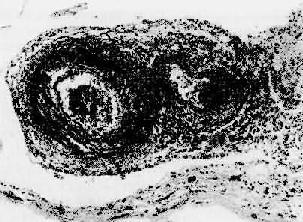

图4-13 结节性多动脉炎

两个动脉壁的各层都有炎性细胞浸润,外膜尤为显著。中膜发生纤维素样坏死